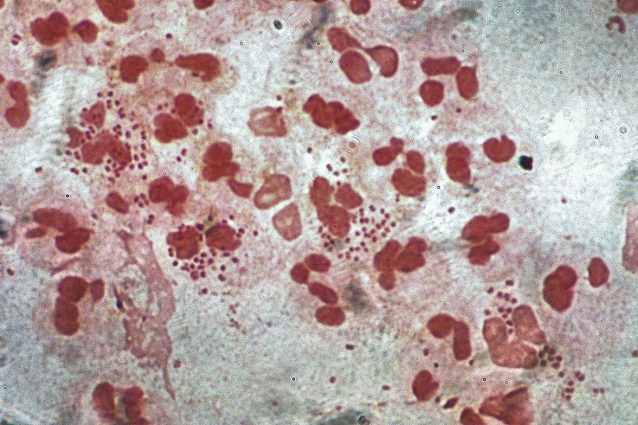

Primi casi di “super gonorrea” rilevati negli USA: il ceppo resiste a cinque antibiotici Ultimissime News, salute, Scienze 23 Gennaio 2023 Due casi di super gonorrea resistente a cinque famiglie di antibiotici sono stati rilevati negli USA. Esperti preoccupati dalla diffusione della malattia sessualmente trasmissibile.Continua a leggere